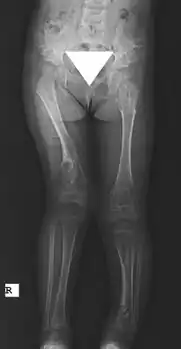

Maffucci syndrome -

X-ray hips and legs: multiple enchondroma -